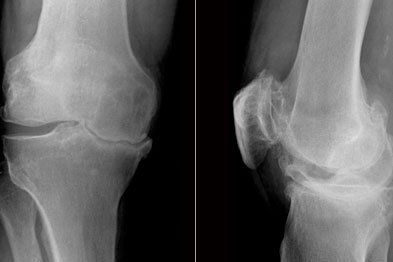

Diagnosis

On examination the person typically presents with:

• Restricted movement

• Widespread mild tenderness

• Lateral or medial joint line tenderness.

There are a number of special tests that help diagnose an ACL injury which include the anterior draw test, lachmann test and pivot shift test. The Lachmann test is the most accurate examination technique and is commonly used.